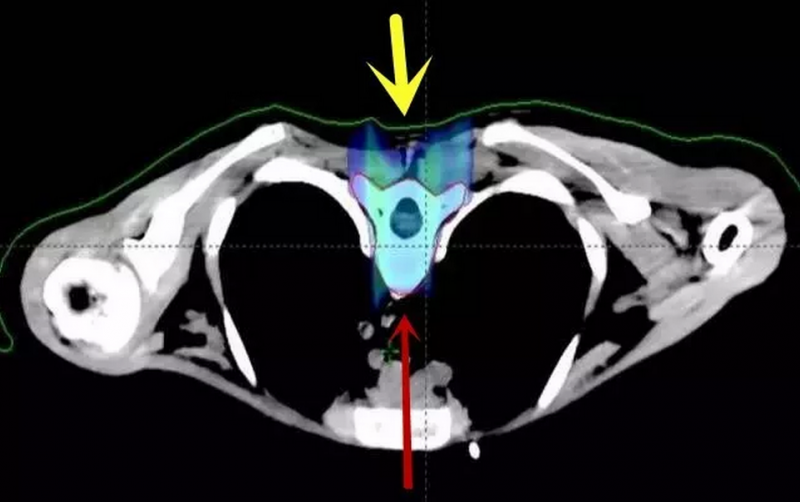

以下为全脑全脊髓质子剂量分布图:脊柱周围心肺胃肠等器官均未受照射

后后颅窝肿瘤区加量质子剂量分布图:其余脑组织未受照射